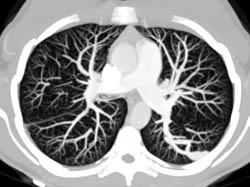

Pulmonary Arteriovenous Malformation (PAVM)